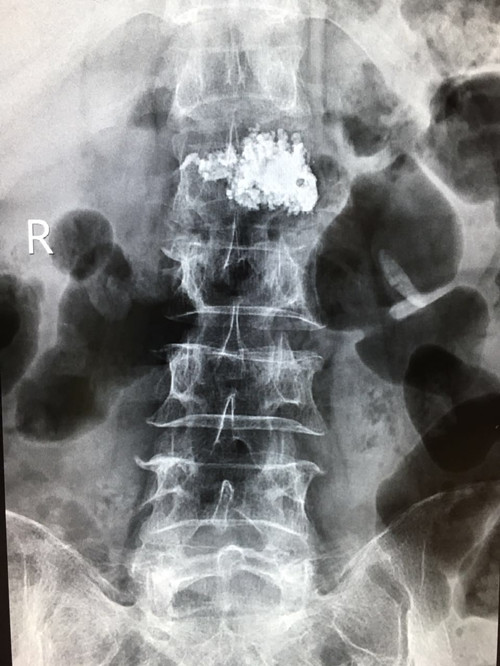

DSA下椎体成形术

一腰痛患者在我院做磁共振检查时发现为腰椎血管瘤,于7月5日下午在DSA下行椎体成形术,手术顺利精准,术后疼痛立即缓解,病人恢复非常好,家属对我院骨科的技术及服务非常满意。